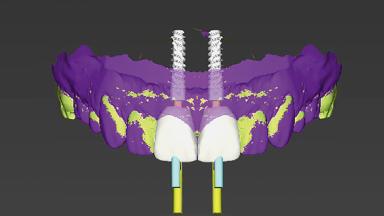

This case from Alejandro Lanis, Luiz Henrique Gonzaga, and Adam Hamilton demonstrates how s-CAIS accurately transfers the virtual treatment plan to the surgical site. In cases where immediacy is indicated, s-CAIS is considered the gold standard to obtain a precise and adequate 3D implant position.